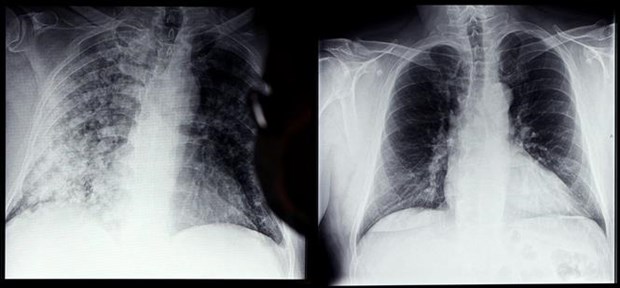

Phim chụp Xquang phổi của bệnh nhân COVID-19 (trái) và phổi của người bình thường tại bệnh viện

ở Magdeburg, miền đông nước Đức, ngày 28/4/2021. (Ảnh: AFP/ TTXVN)